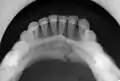

occlusal radiograph of a mandibular parasymphysis fracture

Parasymphysis

Parasymphyseal fractures are defined as mandibular fractures that involve a region bounded bilaterally by vertical lines just distal to the canine tooth.[18]